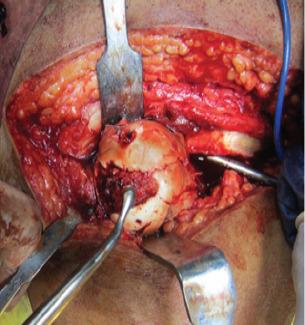

A 23-year-old male who sustained a high-energy trauma due to road traffic accident. He presented to ER with fracture of shaft femur, multi-ligament injury at the ipsilateral knee, fracture lower pole patella, ipsilateral fracture talus, and calcaneus along with comminuted fracture femoral head. He was managed by open reduction and internal fixation of the femoral head by safe surgical dislocation of the hip joint. Such injuries have been described rarely in the literature until now. The purpose of this report is to highlight the extreme rarity, possible mechanism involved, surgical management, and functional outcomes of such injuries.